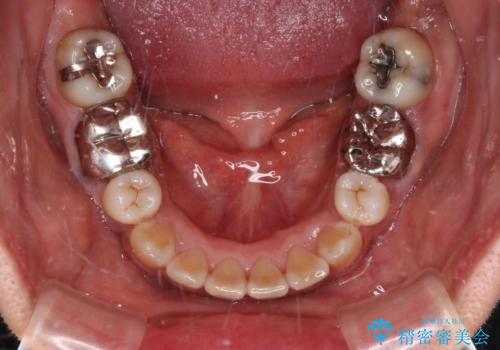

- 矯正治療後に、下顎奥歯の銀歯をすべてゴールドにすることを希望された患者様です。

セラミッククラウンやセラミックインレーによる補綴治療も提案しましたが、お友達にゴールドを自慢したいとのことで、ゴールドクラウンとゴールドインレーにて処置することとしました。